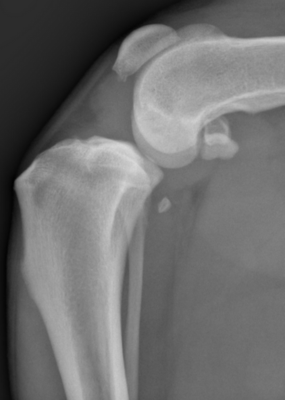

Diagnostic

Le vétérinaire combine plusieurs examens :

- Examen orthopédique spécialisé (test du tiroir) pour détecter la laxité articulaire

- Radiographies pour visualiser anomalies osseuses et arthrose